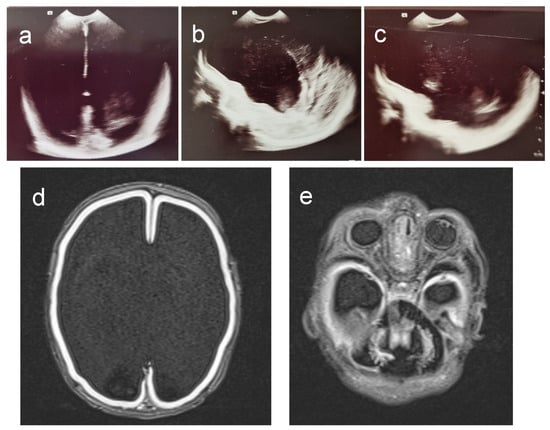

3.1. Clinical Investigations

| cMRI Findings (affected regions) | |

| Basal ganglia | + |

| Cortex | + |

| Corpus callosum | + |

| Cerebellum | + |